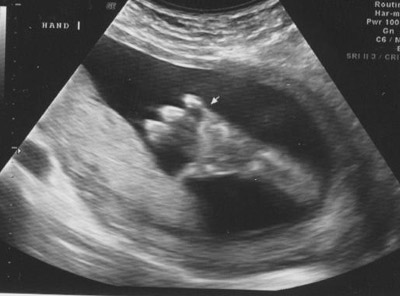

An arm and hand: